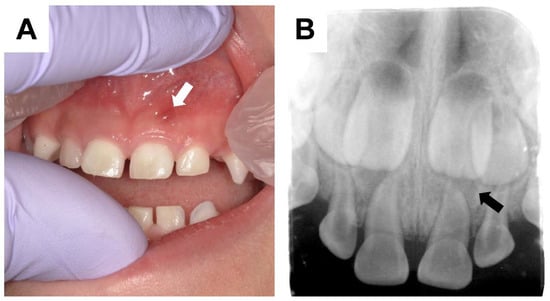

- Douyere, D.; Joseph, C.; Gaucher, C.; Chaussain, C.; Courson, F. Familial hypophosphatemic vitamin D-resistant rickets—Prevention of spontaneous dental abscesses on primary teeth: A case report. Oral Surg. Oral Med. Oral Pathol. Oral Radiol. Endod. 2009, 107, 525–530. [Google Scholar] [CrossRef] [PubMed]

- Lee, B.N.; Jung, H.Y.; Chang, H.S.; Hwang, Y.C.; Hwang, I.N.; Oh, W.M. Dental management of patients with X-linked hypophosphatemia. Restor. Dent. Endod. 2017, 42, 146–151. [Google Scholar] [CrossRef] [PubMed]

- McWhorter, A.G.; Seale, N.S. Prevalence of dental abscess in a population of children with vitamin D-resistant rickets. Pediatr. Dent. 1991, 13, 91–96. [Google Scholar]

- Baroncelli, G.I.; Zampollo, E.; Manca, M.; Toschi, B.; Bertelloni, S.; Michelucci, A.; Isola, A.; Bulleri, A.; Peroni, D.; Giuca, M.R. Pulp chamber features, prevalence of abscesses, disease severity, and PHEX mutation in X-linked hypophosphatemic rickets. J. Bone Miner. Metab. 2021, 39, 212–223. [Google Scholar] [CrossRef] [PubMed]